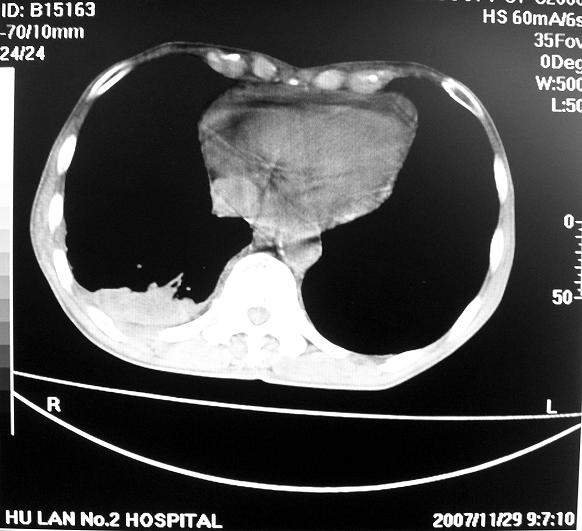

标题: CT10688:男63岁胸痛来诊

男63岁胸痛来诊

右肺病灶前缘不平整,略呈分叶状,其后方胸膜下脂线消失且似有向胸壁浸犯,左下肺球形灶内可见不规则空洞影,余双肺内可见多枚结节影,结合病史支持考虑肺癌肺内转移胸膜转移,便双肺后部病灶倒也是结核好发区域,建议穿刺活检

右下肺周围性肺ca并双肺及右侧胸膜转移。[emb6]

右下肺周围性肺ca并双肺及右侧胸膜转移。支持

右下肺周围性肺ca并双肺及右侧胸膜转移。

右下肺周围性肺ca并双肺及右侧胸膜转移。单看病变像炎性假瘤。

右下肺癌,双肺及胸膜转移

右下肺癌伴双肺及胸膜转移。